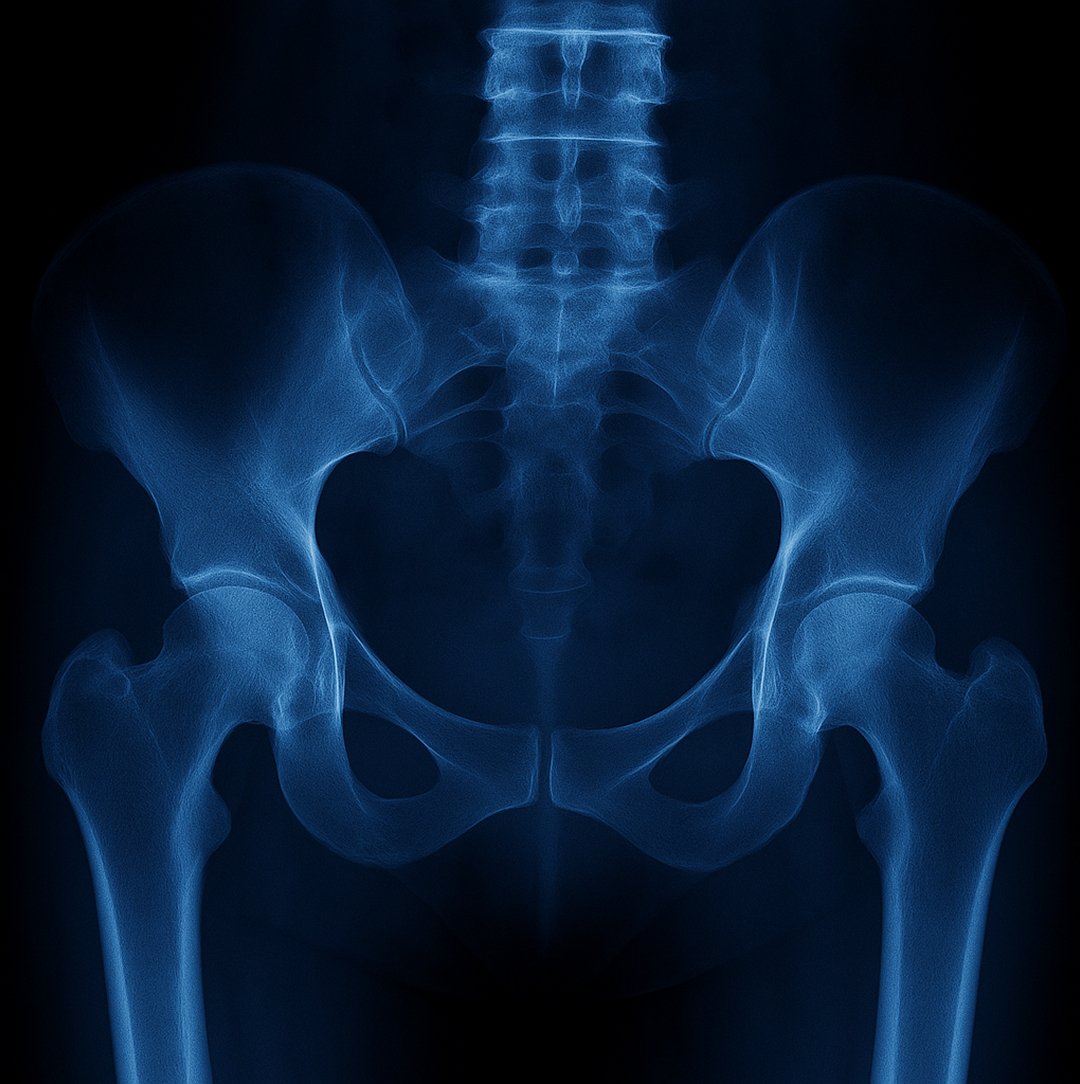

We start with a thorough evaluation of your medical history, symptoms, and the extent of pelvic damage. Using imaging and clinical tests, our specialists develop a treatment plan tailored to your specific needs.

During surgery, damaged or misaligned pelvic structures are stabilised and reconstructed using advanced fixation techniques and implants when necessary. Our surgeons use the latest methods to ensure precision and reduce recovery time.